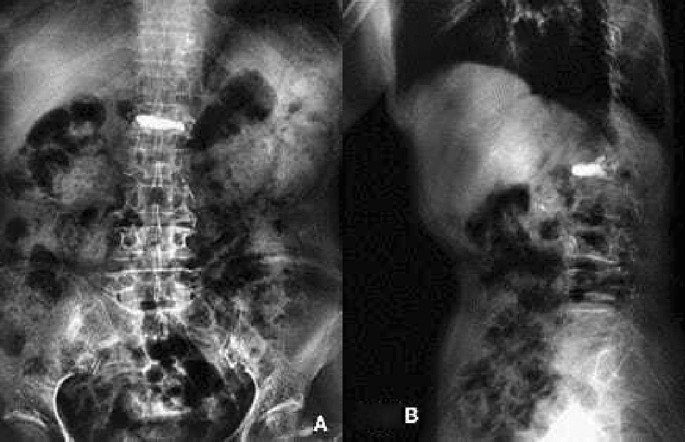

(A) X-ray showing that the bone cement was fully diffused into the vertebral body in the mesh optimization group, (B) X-ray showing the healing of injured vertebral body.

Bone cement injection volume

In the mesh optimization group, the bone cement was fully diffused into the vertebral body (Fig. 3), of which the injection volume was (5.3 ± 2.1) ml; In the traditional PVP group, the bone cement was diffused into the puncture site, but the opposite side was not fully diffused (Fig. 3), of which the injection volume was (4.4 ± 1.5) ml. There was a significant difference in the amount of bone cement injected between the two groups (t = 1.738, P = 0.048). The amount of bone cement injected in the mesh optimization group was higher by 20.5% than in the traditional PVP group.

(A) X-ray showing that the bone cement was diffused into the puncture site in the traditional PVP group, (B) X-ray showing the contralateral side was not fully diffused.